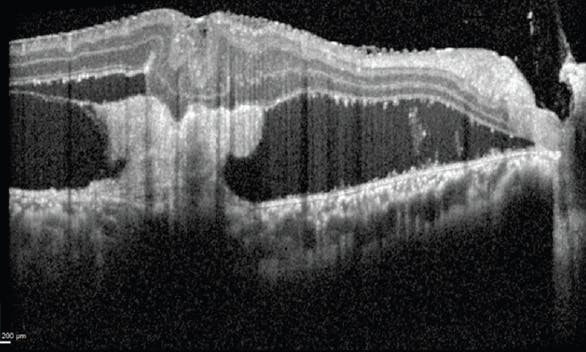

With larger retinectomies, perfluorocarbon liquid is often useful to flatten the retina; in this case, however, the nature of the scleral wound allowed use of a smaller radial retinectomy that ended quite posteriorly, and a fluid-air exchange was sufficient to drain the subretinal fluid. Afterward, two to three rows of laser spots were applied to the retinectomy edge (Figure 1), and silicone oil was inserted as a tamponade.

<p>Figure 1. Two to three rows of laser spots were applied to the edge of the retinectomy that was required to release this patient’s retina from its scleral incarceration site.</p>

Figure 1. Two to three rows of laser spots were applied to the edge of the retinectomy that was required to release this patient’s retina from its scleral incarceration site.